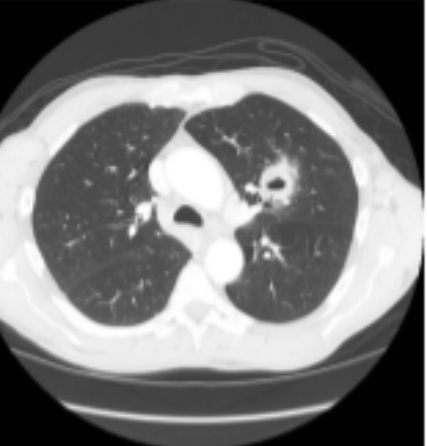

TOMOGRAFIA COM PRESENÇA DE LESÃO CAVITÁRIA EM PULMAO ESQUERDO

1.CÂNCER ?

• *2.TUBERCULOSE

3. ABSCESSO ?**

4.LESÃO FUNGICA ?